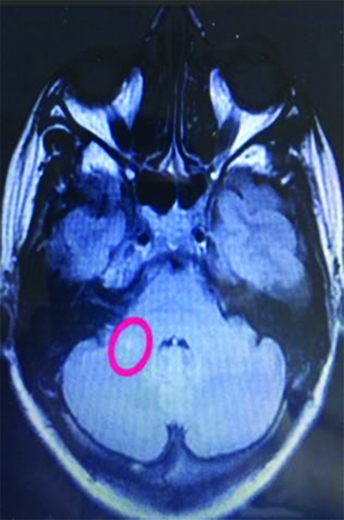

Paciente de 44 años de edad de sexo femenino sin antecedentes clínicos, inicia con deterioro del sensorio de tres semanas de evolución, presentando al examen físico debilidad muscular generalizada, desorientación temporo-espacial, discurso incoherente y conductas bizarras, clasificado como grado III de encefalopatía según la escala de severidad de West Haven. En la resonancia magnética (RM) se observan lesiones múltiples puntiformes como bolas de nieve que confluyen, secuencia de perlas, hiperintensas en secuencia de difusión (DWI) cortico-subcorticales fronto parietal bilateral, cuerpo calloso, unión calloso septal, rodete, hemiprotuberancia y pedúnculo cerebeloso medio derecho en la resonancia magnética (RM Imágenes 1 y 2).

Imagen 1:

RM corte axial de cerebro, (marcado por un anillo rojo) se evidencian lesiones hiperintensas focales y ovoidea, tamaño variable, brillantes, visibles sobre el espesor de cuerpo calloso y en la unión calloso-septal ambos hemisferios cerebrales, aspecto de perlas. Imagen 2: RM corte axial de cerebelo, imagen puntiforme hiperintensa en pedúnculo cerebeloso medio derecho.